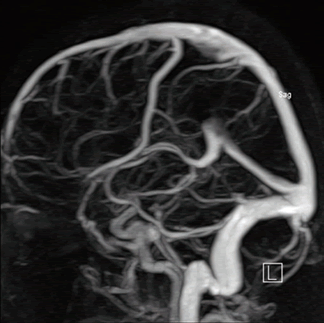

Диагностика магнитно-резонансная ангиография сосудов головного мозга производится при подозрении на тромбофлебит сигмовидного синуса.

Образование тромба является защитной реакцией на проникновение инфекции, но вместе с тем и опасным осложнением тромбофлебита. При маловирулентной инфекции и хороших иммунобиологических реакциях организма тромб может остаться стерильным (известны случаи неожиданного нахождения старого тромба в сигмовидном синусе на МРТ головного мозга (ангиография) и у лиц, умерших от заболеваний, не связанных с ухом). Однако в преобладающем большинстве случаев тромб инфицируется, нередко нагнаивается и сам становится источником инфекции. С током крови инфицированные эмболы или бактерии попадают в малый или большой круг кровообращения.

- МРТ ангиографии сосудов головного мозга с контрастированием